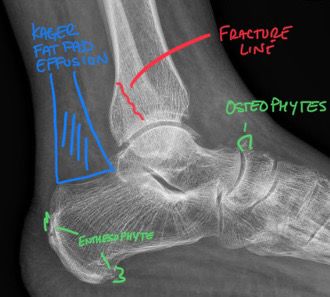

Ankle Sprain Needs a Second Look from Your DACBR or Diagnostic Imaging Consultant

Ankle Sprain Needs a Second Look from Your DACBR (Diagnostic Imaging Consultant)

Ankle Sprain Needs a Second Look from Your DACBR or Diagnostic Imaging Consultant Introduction That “simple ankle sprain” might be